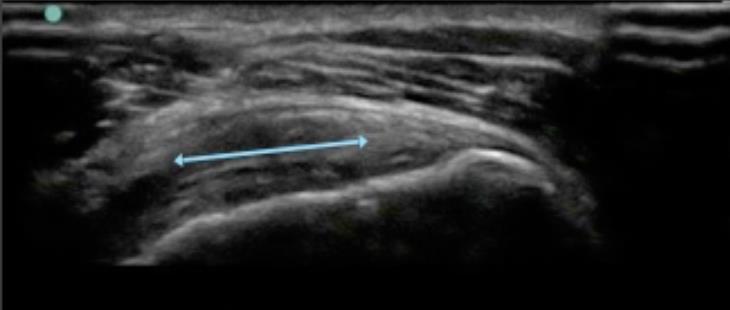

Shoulder Abnormal Infraspinatus Tendon 1 Image